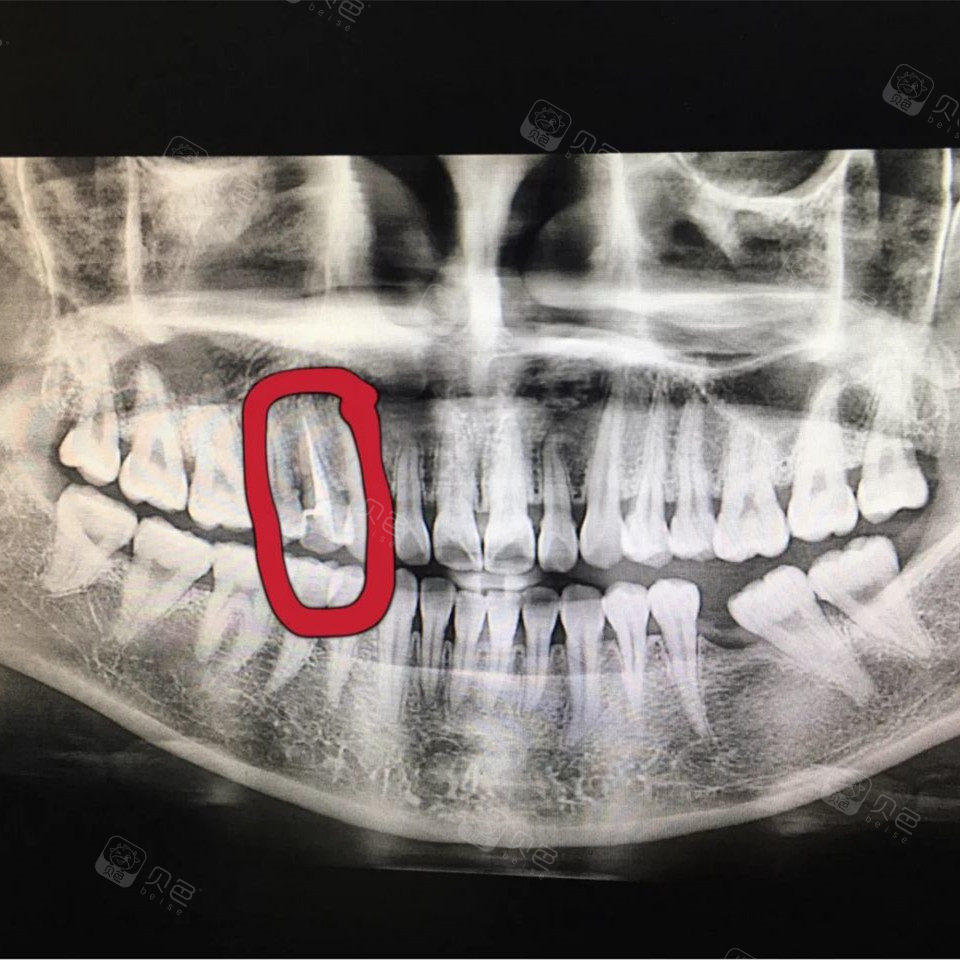

根管治疗片子,根管治疗图片片子

【经典病例】下7根管治疗到修复

遇到这样的牙医也是没办法,只能做根管治疗

发几张根管治疗的片子北京黄巍

一次性根管治疗病例

根管治疗超强解析!

根管治疗图片片子